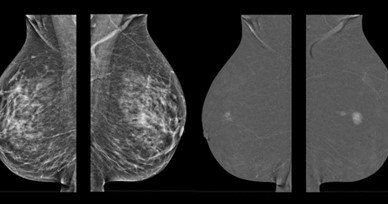

Mammography